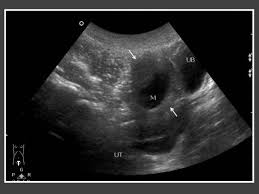

Female Pelvic Ultrasound Tool : Transvaginal Ultrasound Uses And What To Expect : Is the anechoic structure with thin walls actually the bladder or is it an ovarian cyst that needs drainage?

Why You Should Get A Pelvic Ultrasound from improveherhealth.com Is the anechoic structure with thin walls actually the bladder or is it an ovarian cyst that needs drainage? Semin ultrasound ct mr 2008; It allows your doctor to see your bladder, cervix, uterus, fallopian tubes, and ovaries. It is also an important source of diagnostic errors that can have a major impact in patients' management and treatment. An ultrasound of the pelvis is typically used to look at the bladder, ovaries, uterus, cervix, and fallopian tubes (some of these are known as the female reproductive organs). Pelvic ultrasounds are a diagnostic tool that creates images used to assess internal organs in both men and women. Ultrasound is the key screening tool and often the only examination indicated. A pelvic ultrasound is a noninvasive diagnostic exam that produces images that are used to assess organs and structures within the female pelvis.

A pelvic ultrasound is a noninvasive diagnostic exam that produces images that are used to assess organs and structures within the female pelvis. Us is a critical tool in the evaluation of pelvic pain in girls, including those suspected of having acute appendicitis. A transvaginal ultrasound, also called an endovaginal ultrasound, is a type of pelvic ultrasound used by doctors to examine female reproductive organs. Observational study pelvic ultrasound a useful tool in the diagnosis and differentiation of precocious puberty in chinese girls medicine (baltimore). Semin ultrasound ct mr 2008; Female pelvic ultrasound phantom (transvaginal) the pelvic phantom is unique in that it allows for transabdominal and transvaginal scanning. How ultrasound helps perimenopausal patients. A pelvic ultrasound allows quick visualization of the female pelvic organs and structures including the uterus, cervix, vagina, fallopian tubes and ovaries. Tanner breast development score, luteinizing hormone (lh) peak after gona … Owing to the hormonal stimulation of puberty, the uterus enlarges and the fundus becomes prominent. Unfortunately, access to patients can be limited. Pelvic ultrasound (us) is the modality most commonly used to evaluate pelvic anatomy in women, and the finding of a cystic pelvic mass is common. Diagnostic purposes of a pelvic ultrasound include: